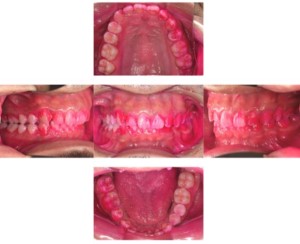

Before

症例

after

歯周病検査(治療前)

歯周病検査(治療後)

レントゲン写真

基本情報

年齢・性別 41歳・男性

主訴 主訴:歯ぐきから出血する

治療部位:全顎

治療内容 1.歯周ポケット検査、資料取り(レントゲン写真14枚・口腔内写真)、歯磨き指導

2.歯磨き指導チェック、縁上の歯石除去

3.縁下の歯石除去4回

4.再評価(歯周ポケット検査・レントゲン写真14枚・口腔内写真)

5.メインテナンス

治療期間 1日

治療費 合計:14,160円

内訳(全て保険診療3割負担)

・初診検査、歯磨き指導、縁上の歯石除去:3,630円

・レントゲン写真、縁下の歯石除去①:3,040円

・縁下の歯石除去②:1,530円

・歯磨き指導チェック、縁下の歯石除去③:2,070円

・縁下の歯石除去④:1,530円

・再評価:2,360円

(2022年5月現在現在)

リスク・副作用 ・歯石除去後すぐは歯ぐきを触っているため歯ぐきに違和感や痛みを感じる場合がある

・歯石除去により今まで腫れていた歯ぐきが引き締まり歯ぐきが下がる可能性がある

・歯ぐきが引き締まって下がることにより歯面が今までより露出し知覚過敏の症状がでる可能性がある

・歯石除去後、歯磨きを怠ると細菌が歯周ポケットのより深部まで入ってしまうため歯周病が悪化してしまう可能性がある

・一度歯周病になると再発しやすい為、定期的なメインテナンスが必要になります

治療方針 1.歯磨き指導

2.歯ぐき上の歯石除去

3.歯ぐき下の歯石除去

4.再評価

5.定期的なメインテナンス

特記事項 ・着色除去(PMTC)は自費治療のため希望しませんでした。

・右下7番の歯周ポケット5mmは親知らずの関係もあり、このまま維持していくことを説明しています。

・他4mmの歯周ポケットに関しては歯垢が少し残っていた為、再度歯磨き指導と、縁下の歯石を確認して様子をみることにしました。

担当者所見 全体的に出血が見られたのと、奥の歯ぐきは炎症があり歯周ポケットが深かった為、まずは歯ブラシの当て方+歯間ブラシ3Sサイズを使用して頂き炎症を落ち着かせました。

両方毎日使用して頂いた為、スムーズに歯周病治療を行うことができました。毎日のホームケアが不十分だと、なかなか結果に繋がらず、治療期間も長くかかってしまう為、患者様の協力が歯周病治療を成功させるためにはかなり重要になっていきます。

そして一度病気になった歯ぐきは再発しやすい為、今後は3ヶ月に1度の定期的なメインテナンスで、この状態を維持できるよう一緒に管理していきます。